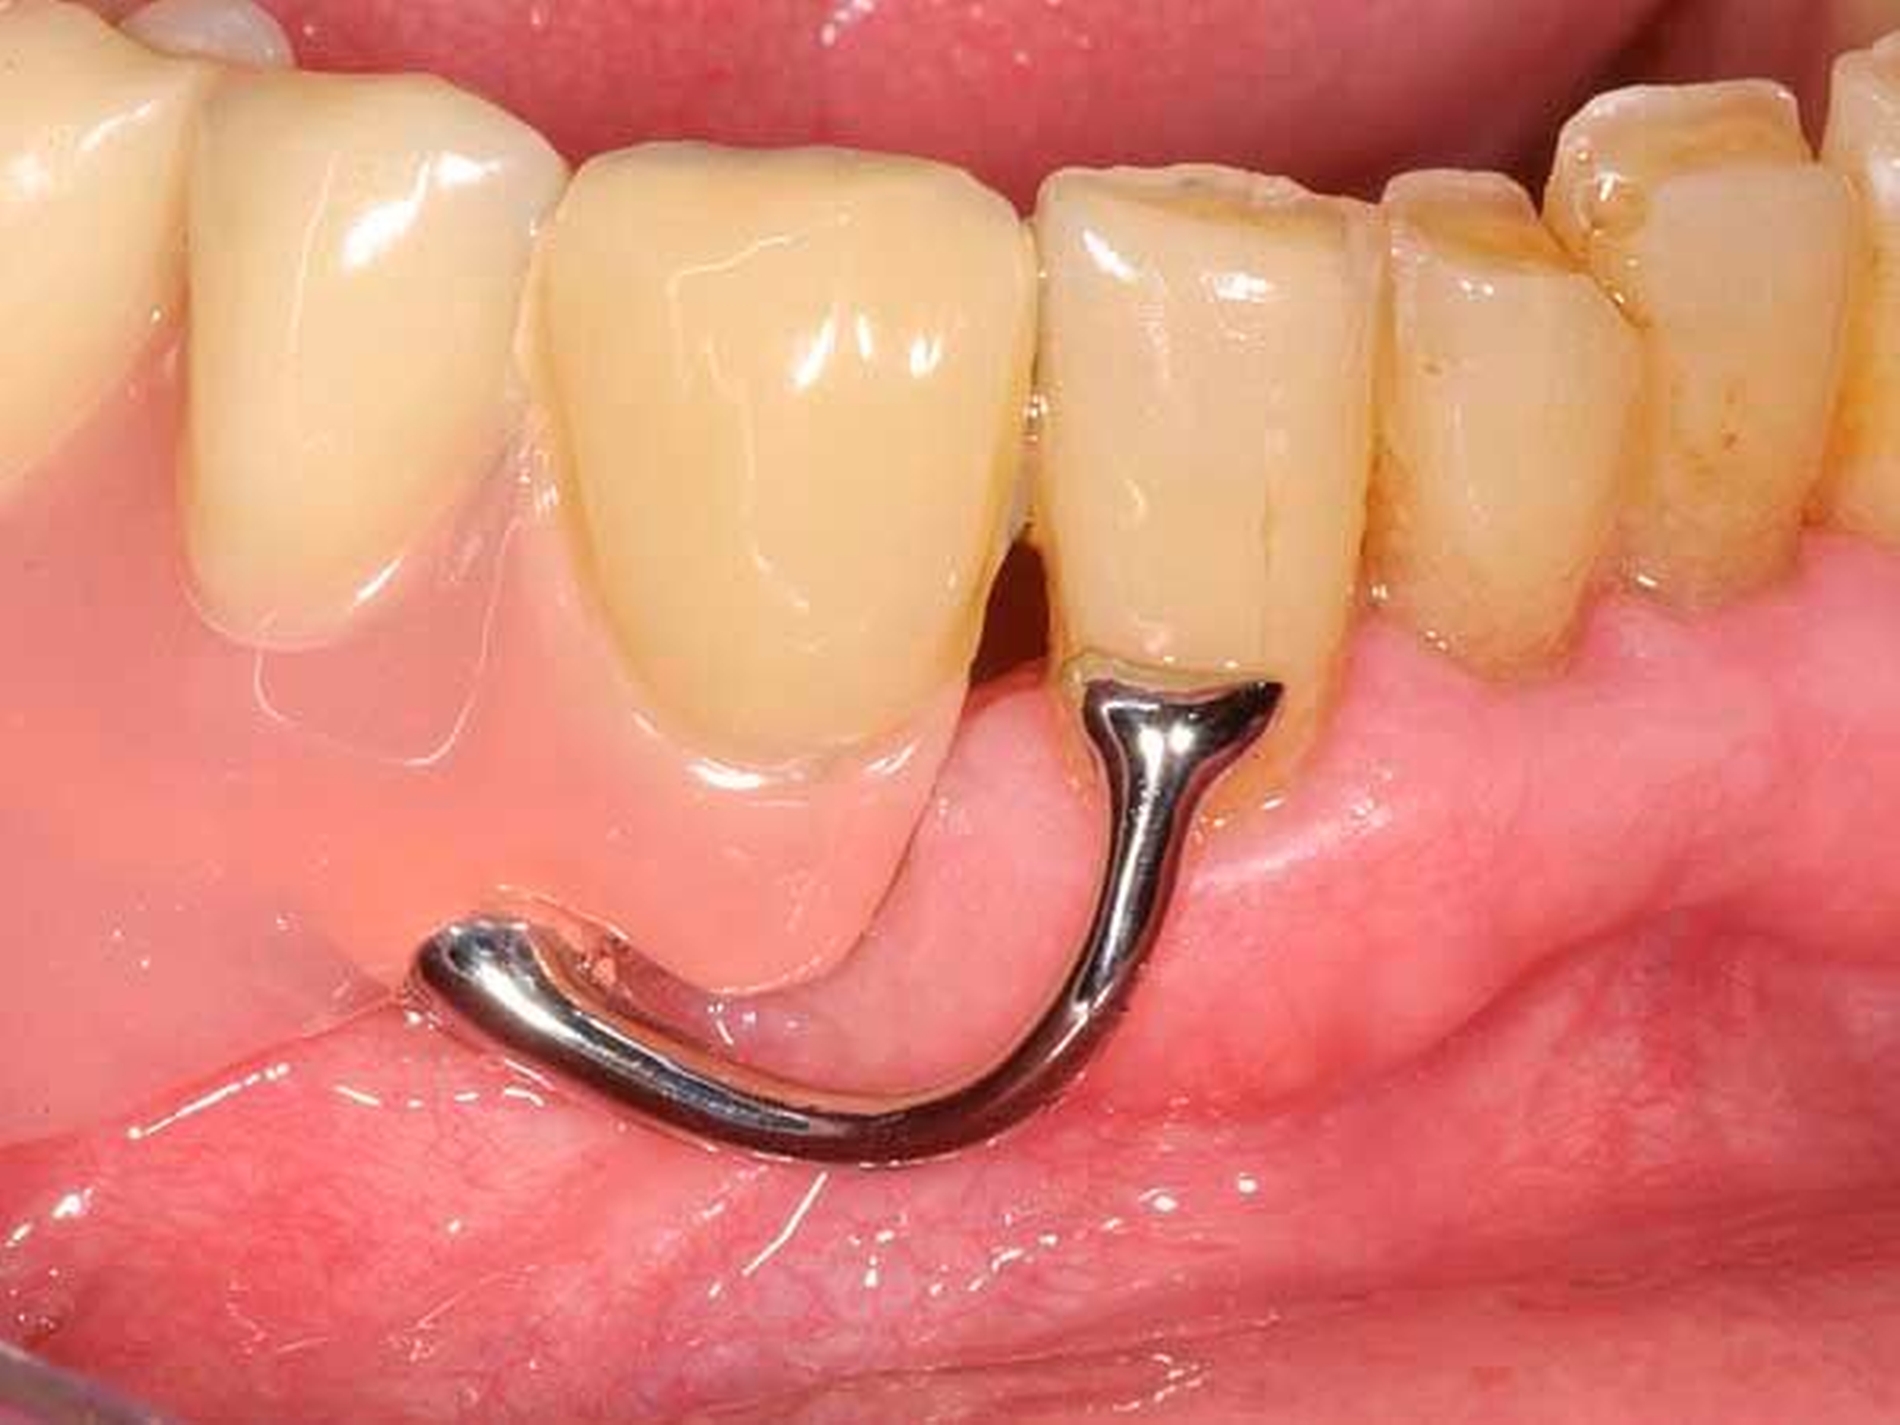

Die Patientin konnte mit einer Modellgussprothese und zwei RPI-Klammern an den Zähnen 34 und 45 erfolgreich versorgt werden (Abbildungen 3 und 4). RPI steht für Rest (meist sattelferne Abstützung), Proximal Plate (approximale Führungsfläche), l-bar (i-förmiger Retentionsteil). Das RPI-Klammersystem wurde 1963 von Kratochvil [Kratochvil, 1963] eingeführt und von Krol 1973 [Krol, 1973] weiterentwickelt. Das Klammersystem ist kein Exot. Es findet sich in nahezu allen internationalen Standardlehrbüchern der Prothetik und gilt als das mit am besten bewährte Klammersystem für die bilaterale Freiendsituation [Davenport et al., 1992; Krol, 1999; Carr et al., 2000].

Die proximale Platte der RPI-Klammer blockiert wirkungsvoll dislozierende Sattelbewegungen (Abbildung 5), der von gingival inserierende Retentionsarm ist nahezu unsichtbar. Aufgrund des langen Federweges ist der Retentionsarm praktisch ermüdungsfrei und lässt sich gegebenenfalls leicht aktivieren. Die Abstützung liegt sattelfern analog einer Back-Action-Klammer. Für die RPI-Klammer wird am Ankerzahn neben der üblichen mesialen Klammerauflage die disto-approximale Wand parallel zur Einschubrichtung im Schmelz präpariert (Abbildung 6). Die Präparation sollte mindestens 1 mm oberhalb der Papille enden. Die präparierte Fläche dient der flächigen Anlage der proximalen Platte (Abbildung 3).